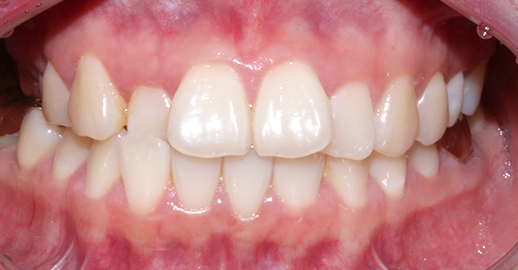

[4개월 교정이 끝난 모습]

4개월만에 가지런하게

치열이 바뀐 모습입니다.

생각보다 더 빠르게

교정이 끝났는데요 ^_^

치아 모양도 고르고 예쁘게

잘 교정되었습니다.

전체 교정만큼 고생하지 않고

빠른 기간동안 개선되어

환자분도 굉장히 만족하셨습니다.